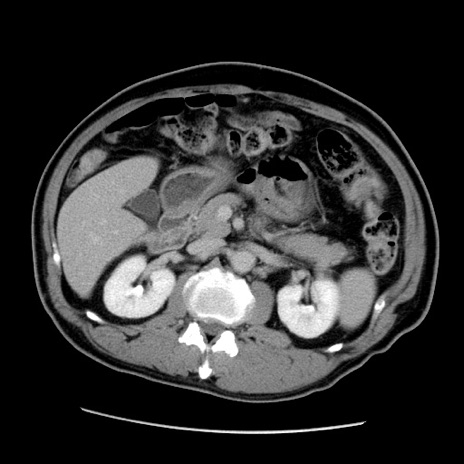

症例22(横断像)

【症例】50歳代男性

【主訴】腹痛

【現病歴】AVMからの被殻出血のため回復期リハ病棟入院中。 本日午後3時頃急に下腹部痛が出現した。

【既往歴】AVM、被殻出血、虫垂炎、高血圧

【身体所見】意識晴明、左半身不全麻痺、会話の理解は良好、36.5°C、腹部:膨隆、全体に板状硬、下腹部正中に圧痛点あり、反跳痛-、筋性防御不明、右下腹部にope scar

【データ】WBC 9400、CRP 0.06